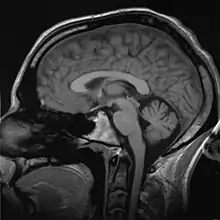

Medical imaging

Medical/biomedical imaging is a major segment of medical devices. This area deals with enabling clinicians to directly or indirectly "view" things not visible in plain sight (such as due to their size, and/or location). This can involve utilizing ultrasound, magnetism, UV, radiology, and other means.

Imaging technologies are often essential to medical diagnosis, and are typically the most complex equipment found in a hospital including: fluoroscopy, magnetic resonance imaging (MRI), nuclear medicine, positron emission tomography (PET), PET-CT scans, projection radiography such as X-rays and CT scans, tomography, ultrasound, optical microscopy, and electron microscopy.